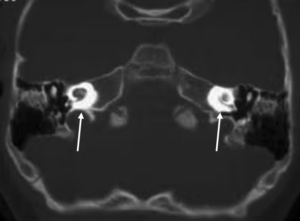

Bilgisayarlı tomografi (BT). İç kulaktaki iltihabın iç kulağın etrafındaki yapılarla, örneğin orta kulak ile olan ilişkisini değerlendirmekte yararlanılır. Bu iltihabın sonrasında gelişebilen iç kulak taşlaşmasının tanısında da altın standart tanı yöntemidir (Şekil 2).

Şekil 2. İç kulak taşlaşması. İki kulakta da iç kulak iltihabının iyileşmesi sırasında istenmeyen bir sonuç olan taşlaşmanın bilgisayarlı tomografi görüntüsü. Beyaz oklar bu durumu göstermektedir.